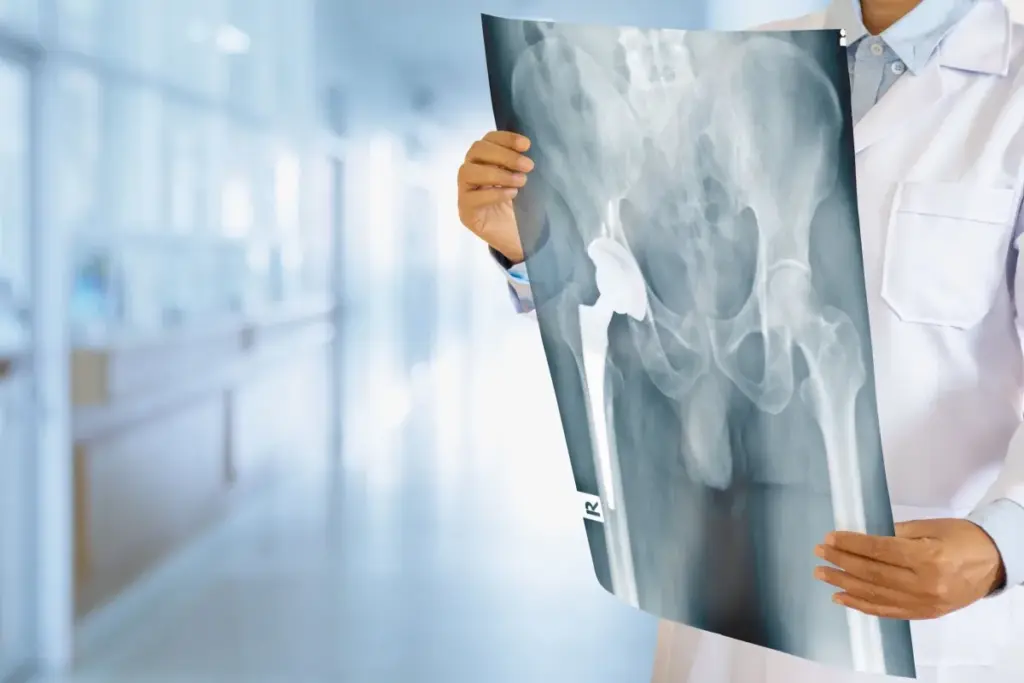

Understanding Hip Replacement Surgery

It’s important for patients to understand hip replacement surgery. This surgery, also known as hip arthroplasty, is for hip pain and stiffness. It’s often due to arthritis or fractures.

Types of Hip Replacement Procedures

There are many types of hip replacement surgeries. Each one is chosen based on the patient’s needs. The most common is total hip replacement. This involves replacing both the acetabulum and the femoral head with prosthetics.

What Happens During Hip Replacement Surgery

During hip replacement surgery, a surgeon replaces the damaged hip with a prosthetic. This is done to ease pain and improve movement for those with severe hip issues.